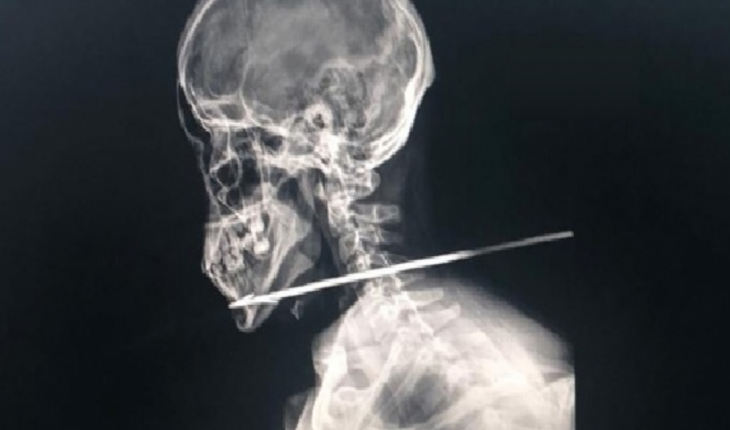

Um jovem de 21 anos foi atacado com uma flecha quando tentava atravessar a fronteira da Guiana Francesa com o Brasil.